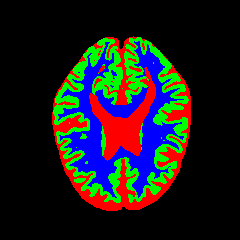

7 Qualitative Evaluation

Fig. 8 and Fig. 10 provide qualitative comparisons on the OASIS-1 and MRBrainS13 datasets, respectively. It is visually evident that the baseline predictions (c) and standard augmentations (e.g., (d), (g), (i)) frequently suffer from noisy artifacts, blurred boundaries, and mis-segmentation of intricate anatomical structures. In stark contrast, our ”Ours+” enhanced methods (e.g., (e), (h), (k)) consistently produce segmentation maps that are visibly cleaner, more spatially coherent, and demonstrate significantly sharper adherence to the Ground Truth (b). This superior fidelity is particularly noticeable in the complex sulcal patterns and holds true across all three backbones (rows), confirming that our framework yields more robust and anatomically plausible results.